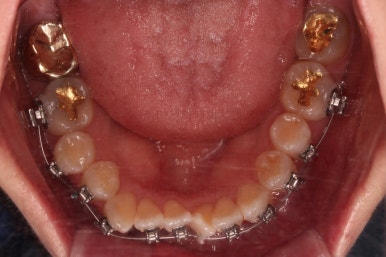

3. 치료과정

개방교합을 닫는 전략은 앞니를 약간 끌어내리고, 어금니를 앞니 위치로 약간 올려서 균형을 맞추는 건데요.

여전히 앞니는 내버려둔 채로, 윗니는 어금니쪽만 진행하며 아랫니도 장치를 부착했습니다.

난이도가 매우 높은 치료인만큼 미니스크류의 구성과 장치 구성도 매우 복잡했는데요.

윗니 어금니를 뒤로 밀면서 앵글씨 2급 부정교합을 개선해 주고, 높낮이를 조절하면서 개방교합을 개선해 줍니다.

개방교합도 많이 다물어졌고, 2급 부정교합도 매우 많이 개선되었네요.